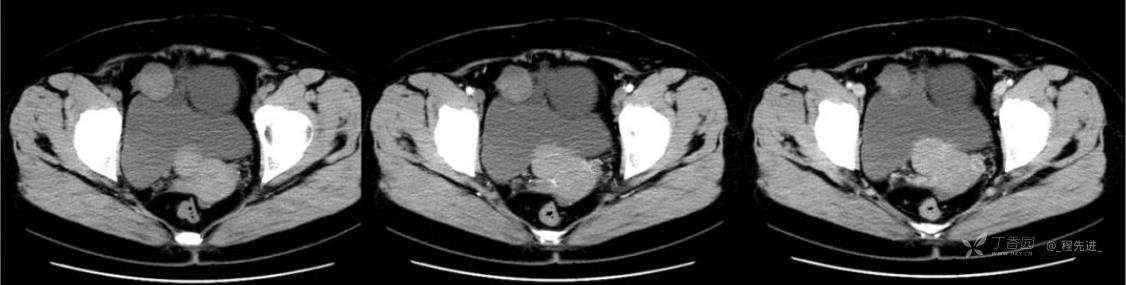

1月特别精彩病例|中老年女性,盆腔包块近半年持续增大【病理已公布】

患者年龄:53岁

简要病史:4年前体检时发现盆腔包块及子宫肌瘤,近半年复查盆腔彩超发现包块持续增大,近1年月经欠规律,伴腰、腹胀。

体格检查:宫颈举痛(+),子宫增大,质地中等,活动可,无压痛;右下腹轻压痛,无反跳痛,左侧附件区未扪及明显包块,无压痛。

阴式彩超:子宫约65*58*44mm大小,子宫肌层可见多个低回声块影,较大的为35*27mm(位于子宫前壁下段偏右侧壁),边界清,内回声欠均匀,后方回声衰减。考虑子宫多发肌瘤。子宫后壁可见一混合回声包块,大小约31*20mm,边界不清,内呈强弱回声,分布不均,考虑子宫腺肌瘤,其他疾患待删。子宫内膜厚6mm,宫颈可见多个囊性暗区,边界清,内透声好,后壁效应增强,较大的为15*11mm。子宫前方偏左侧可探及一大小89*75mm囊性肿块,边界清,壁薄光滑,内透声好,可见分隔光带